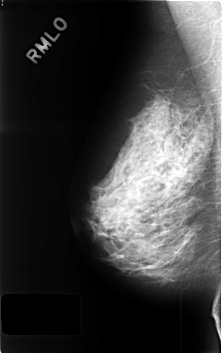

ics_version 1.0 filename C-0440-1 DATE_OF_STUDY 21 7 1995 PATIENT_AGE 48 FILM FILM_TYPE REGULAR DENSITY 3 DATE_DIGITIZED 23 11 1998 DIGITIZER LUMISYS LASER SEQUENCE LEFT_CC LINES 4584 PIXELS_PER_LINE 2912 BITS_PER_PIXEL 12 RESOLUTION 50 NON_OVERLAY LEFT_MLO LINES 4592 PIXELS_PER_LINE 2880 BITS_PER_PIXEL 12 RESOLUTION 50 OVERLAY RIGHT_CC LINES 4552 PIXELS_PER_LINE 2920 BITS_PER_PIXEL 12 RESOLUTION 50 NON_OVERLAY RIGHT_MLO LINES 4584 PIXELS_PER_LINE 2888 BITS_PER_PIXEL 12 RESOLUTION 50 NON_OVERLAY |